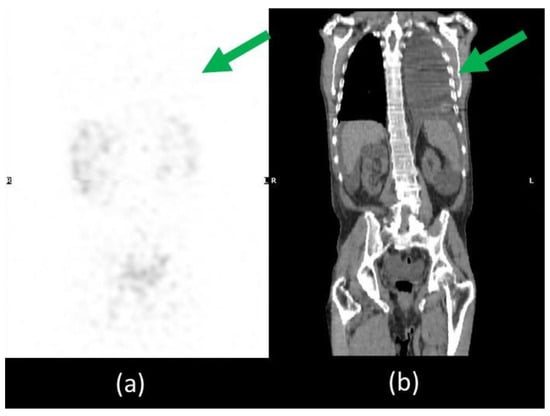

Unfortunately, he was readmitted 7 days later with abdominal distension and dyspnoea. During hospitalization, thorax and abdominal contrast-enhanced CT was performed which confirmed a massive ascites and described the presence of left pleural effusion without the presence of liver diseases (Figure 1).

Coronal (a) and sagittal (b) abdominal CECT showed massive ascites in supra and inframesocolic recesses. Non-hepatic diseases were recorded. (c) Sagittal thorax CECT demonstrated left pleural effusion.

Furthermore, thorax SPECT/CT did not show radioactivity distribution in the left pleural effusion excluding the presence also of chylothorax and demonstrating its reactive aetiology of it (Figure 5).

Figure 5.

SPET/CT whole body lymphoscintigraphy. MIP image (a) did not show any radiotracer uptake in the left pleural effusion visible on CT coronal image (b), excluding the presence of chylothorax (green arrow).